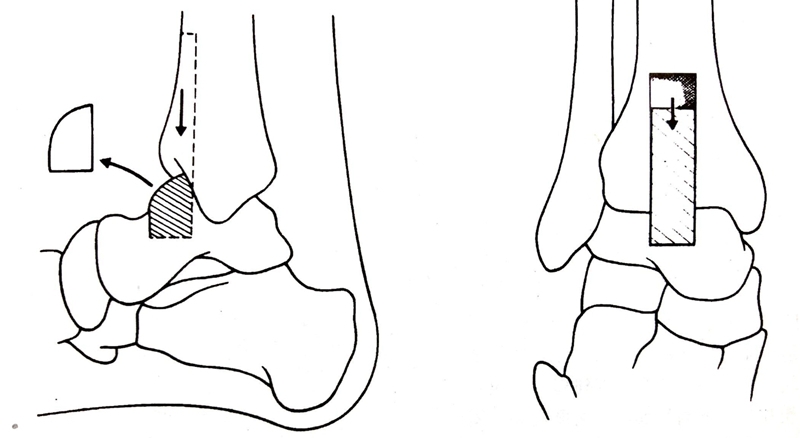

4. 从胫骨远端前侧用电锯截取一条8×2.5cm长方形骨块,在距骨颈上方做一深2cm的横行槽,将胫骨植骨块滑入槽中。

足保持在背屈度,外翻5度,外旋10度的位置上,用螺钉将植骨块近端固定到胫骨上。

通过跟骨纵向向上穿入一枚斯氏针,深度达到经骨远端3-10cm处,增加稳定性,植骨。

①将距骨后移,胫骨远端的前面与距骨头和颈的连接处在一条线上。距骨后移减少了足前方力臂的长度,使步态更接近正常。

②再通过跟骨纵行向上穿入斯氏针,达到胫骨远端上5-10cm

③融合角度:屈曲度、外翻-5度、外旋5-10度(胫骨结节与第一趾蹼成一直线),距骨轻度向后移位。踝功能位男性90度,女性可95-100度。

④胫骨骨瓣 10x2.5x1cm8x2x0.8cm